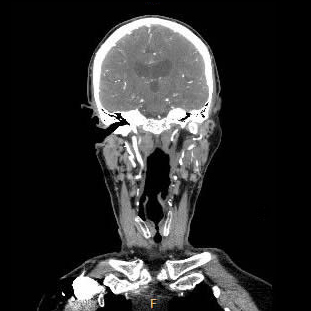

| Computertomographie mit aktuellen Dosisreduktionsverfahren | ||

| Kopf | 1-2 | |